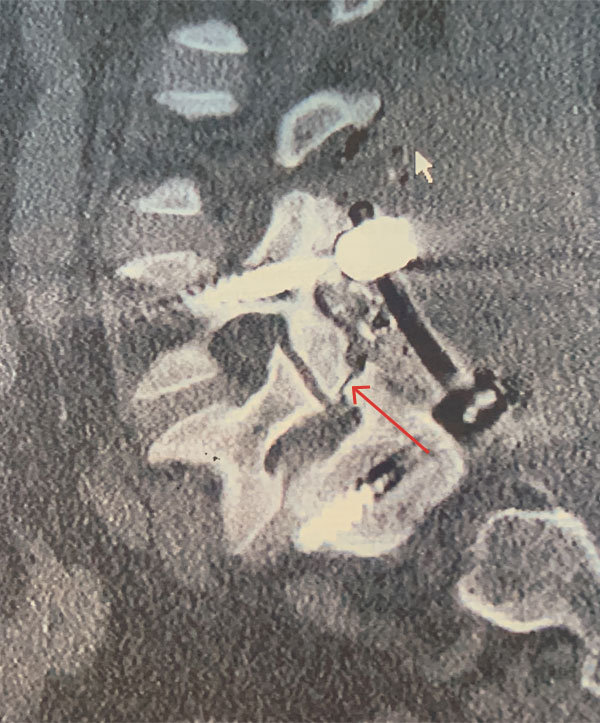

MRI of the lumbar spine (Fig. 1) demonstrated a grade 1-2 spondylolisthesis at L5-S1 with bilateral pars defects with significant L5-S1 foraminal compression. She had an associated L4-5 retrolisthesis with secondary degenerative changes with a dysmorphic trapezoidal L5 vertebral body.

Figure 1: Sagittal MRI T2-Weighted image of lumbar spine demonstrating grade 1 L5-S1 spondylolisthesis and retrolisthesis of L4-5 with significant degenerative disease of both segments. Note dysmorphic L5 vertebral body (arrow).

Figure 3 – Sagittal CT image showing post placement of posterior segmental fusion L4-S1 construct. Note pars deflect of L5 (arrow).